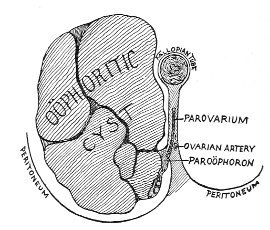

The origin of vaginal cysts has been much disputed. It is probable that they arise from the remains of the Wolffian canal—the canal of Gärtner. In the embryo the transverse or longitudinal tubule of the parovarium extends to the side of the uterus and thence down the side of the vagina to the urethral orifice. It persists in this condition in some of the lower animals—the sow and the cow—and may also persist as a closed tube in woman. In such cases it may become distended and form the vaginal cyst.